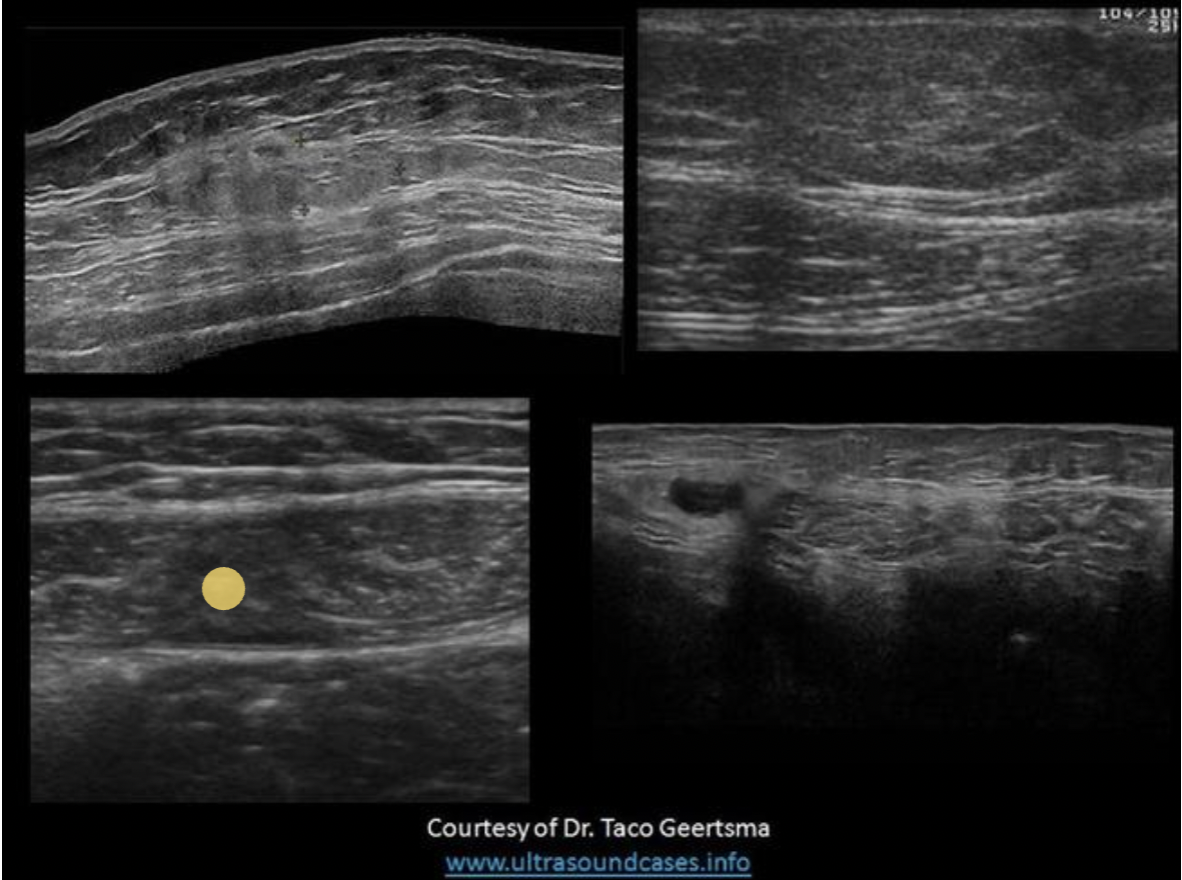

Find the rectus sheath hematoma

Top left is a benign mass with lobulated borders and the top right is a lipoma. Both are located in the subcutaneous tissues/fat between the skin and the anterior rectus sheath. The lipoma has smooth borders and an echogenicity similar to the surrounding fat.

The bottom right image demonstrates a spigelian hernia, between the right rectus abdominis and right oblique muscles.

The bottom left image demonstrates a hematoma in the rectus abdominis muscle, between the anterior and posterior rectus sheaths.

Find the lipoma

The top two images demonstrate solid masses that are superficial to the rectus abdominis muscle. Top left is a benign mass with lobulated borders and the top right is a lipoma. Both are located in the subcutaneous tissues/fat. The lipoma has smooth borders and an echogenicity similar to the surrounding fat.